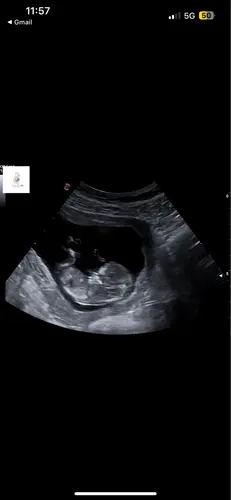

Ik heb eergisteren de nipt test laten doen. Op de 12 weken echo zag alles er voorlopig heel mooi uit. Nekplooi was 1,04. Toch maak ik me door mijn vorige miskraam enorm veel zorgen of alles goed is en maakt het gedacht dat ik nog zo lang moet wachten op de uitslag me gek… is er nog een grote kans dat er toch iets uit de nipt komt?